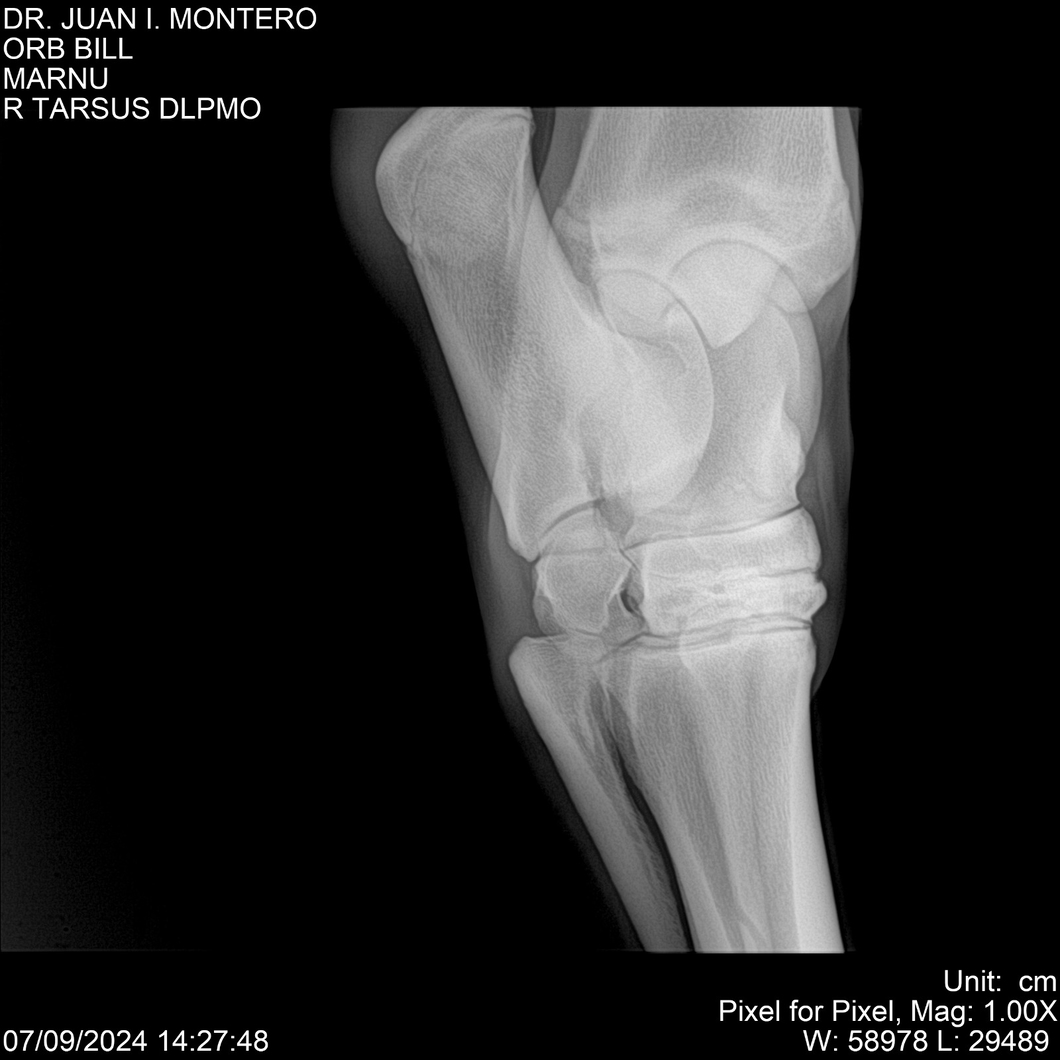

LOTE 7, ORB BILL 🔥 🔥 🔥 Lote Anterior Volver al remate Lote Siguiente Ficha Contacto Montevideo - Ficha del Lote Identificador: #282523 Categoría: Yeguarizos Montevideo - 83 Visualizaciones ClicData Contacto Empresa: Abelenda N. R., Walter Hugo Nombre*: Teléfono* : E-mail* : Mensaje Enviar Registrese gratis Este contenido Exclusivo está disponible sólo para usuarios registrados Ingresar